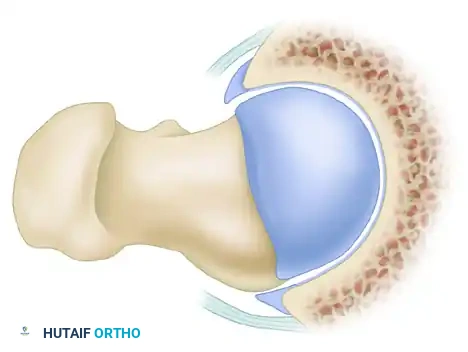

Cam Impingement

Cam impingement is predominantly observed in young, active male patients. It is characterized by an abnormally shaped, nonspherical femoral head with a decreased head-neck offset. This aspherical extension of the epiphysis (often referred to as a "pistol grip" deformity) creates a cam effect as the femoral head rotates into the acetabulum.

During dynamic hip flexion and internal rotation, the prominent cam lesion forcefully abuts the anterosuperior acetabular rim. Because the cam lesion is larger than the corresponding acetabular opening, it acts as a wedge, generating massive shear forces across the articular surface.

Over time, this repetitive shearing leads to delamination of the acetabular cartilage from the subchondral bone and subsequent avulsion or detachment of the labrum from the articular margin. The labrum itself is often pushed outward, resulting in an "outside-in" pattern of failure.

Pincer Impingement

Pincer impingement is most commonly identified in middle-aged women and is characterized by focal or global overcoverage of the femoral head by the acetabulum.

In pincer impingement, the abnormal contact occurs directly between the prominent acetabular rim and the structurally normal femoral head-neck junction. This linear contact crushes the labrum between the bone of the femoral neck and the acetabular rim, causing intrasubstance tears and ossification of the labrum.

Clinical Pearl: The Contrecoup Lesion

As pincer impingement progresses and the anterior femoral neck repeatedly strikes the anterior acetabular rim, the femoral head is levered out of the socket posteriorly. This subluxation force drives the posteromedial femoral head into the posteroinferior acetabulum, creating a secondary "contrecoup" chondral injury in the posterior joint space.